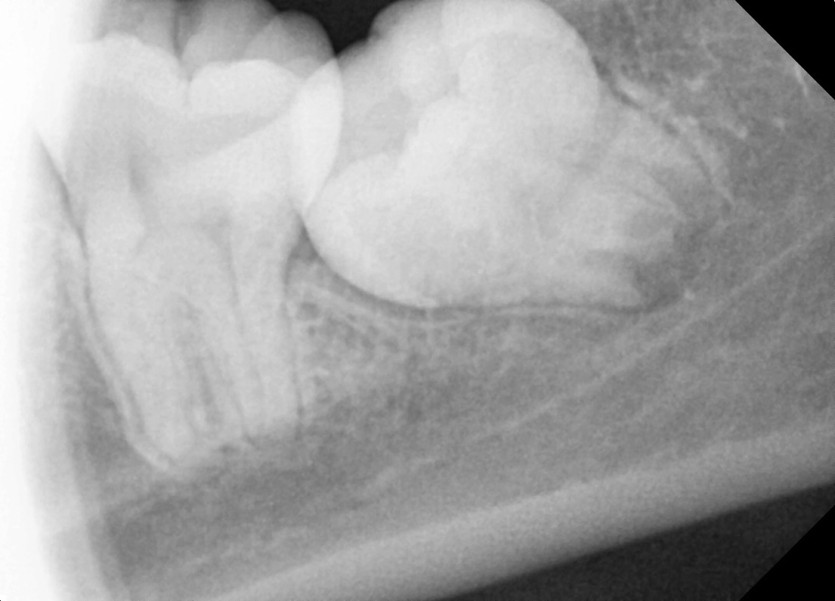

#38,48 사랑니 발치

구강 외과 전문의가 당일 발치했습니다.